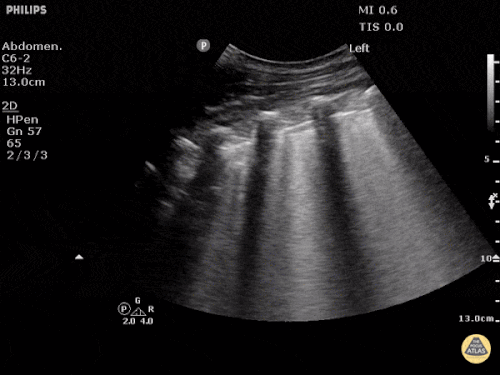

Pleurale Flüssigkeit

Neben der Lunge selbst, wird natürlich auch die Pleurahöhle untersucht. Hier wird nach Flüssigkeit gesucht als Zeichen für einen Pleuraerguss oder Hämatothorax. Diese Flüssigkeitsansammlung kann durch Verdrängung der mediastinalen Strukturen hämodynamische Relevanz erlangen.

Quelle: http://www.thepocusatlas.com/pulmonary CC BY-NC 4.0